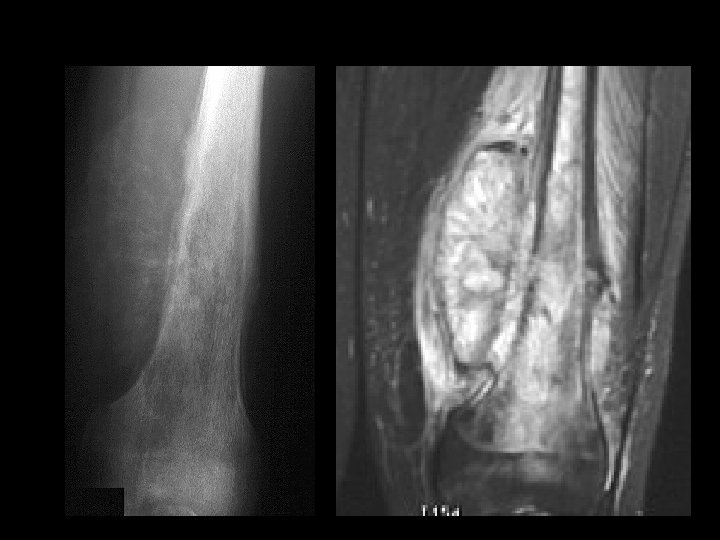

A 14 year old boy presents with pain and a mass above the knee. Take a look at the AP and lateral radiographs first.

Cross-sectional imaging Pictures are pretty, but diagnosis • established at histology MRI best for most tumors • optimal results at sites with experience – Role of CT limited • may assist in assessing tumor matrix – useful in directing biopsy –

Example 10

Example 10

Example 11